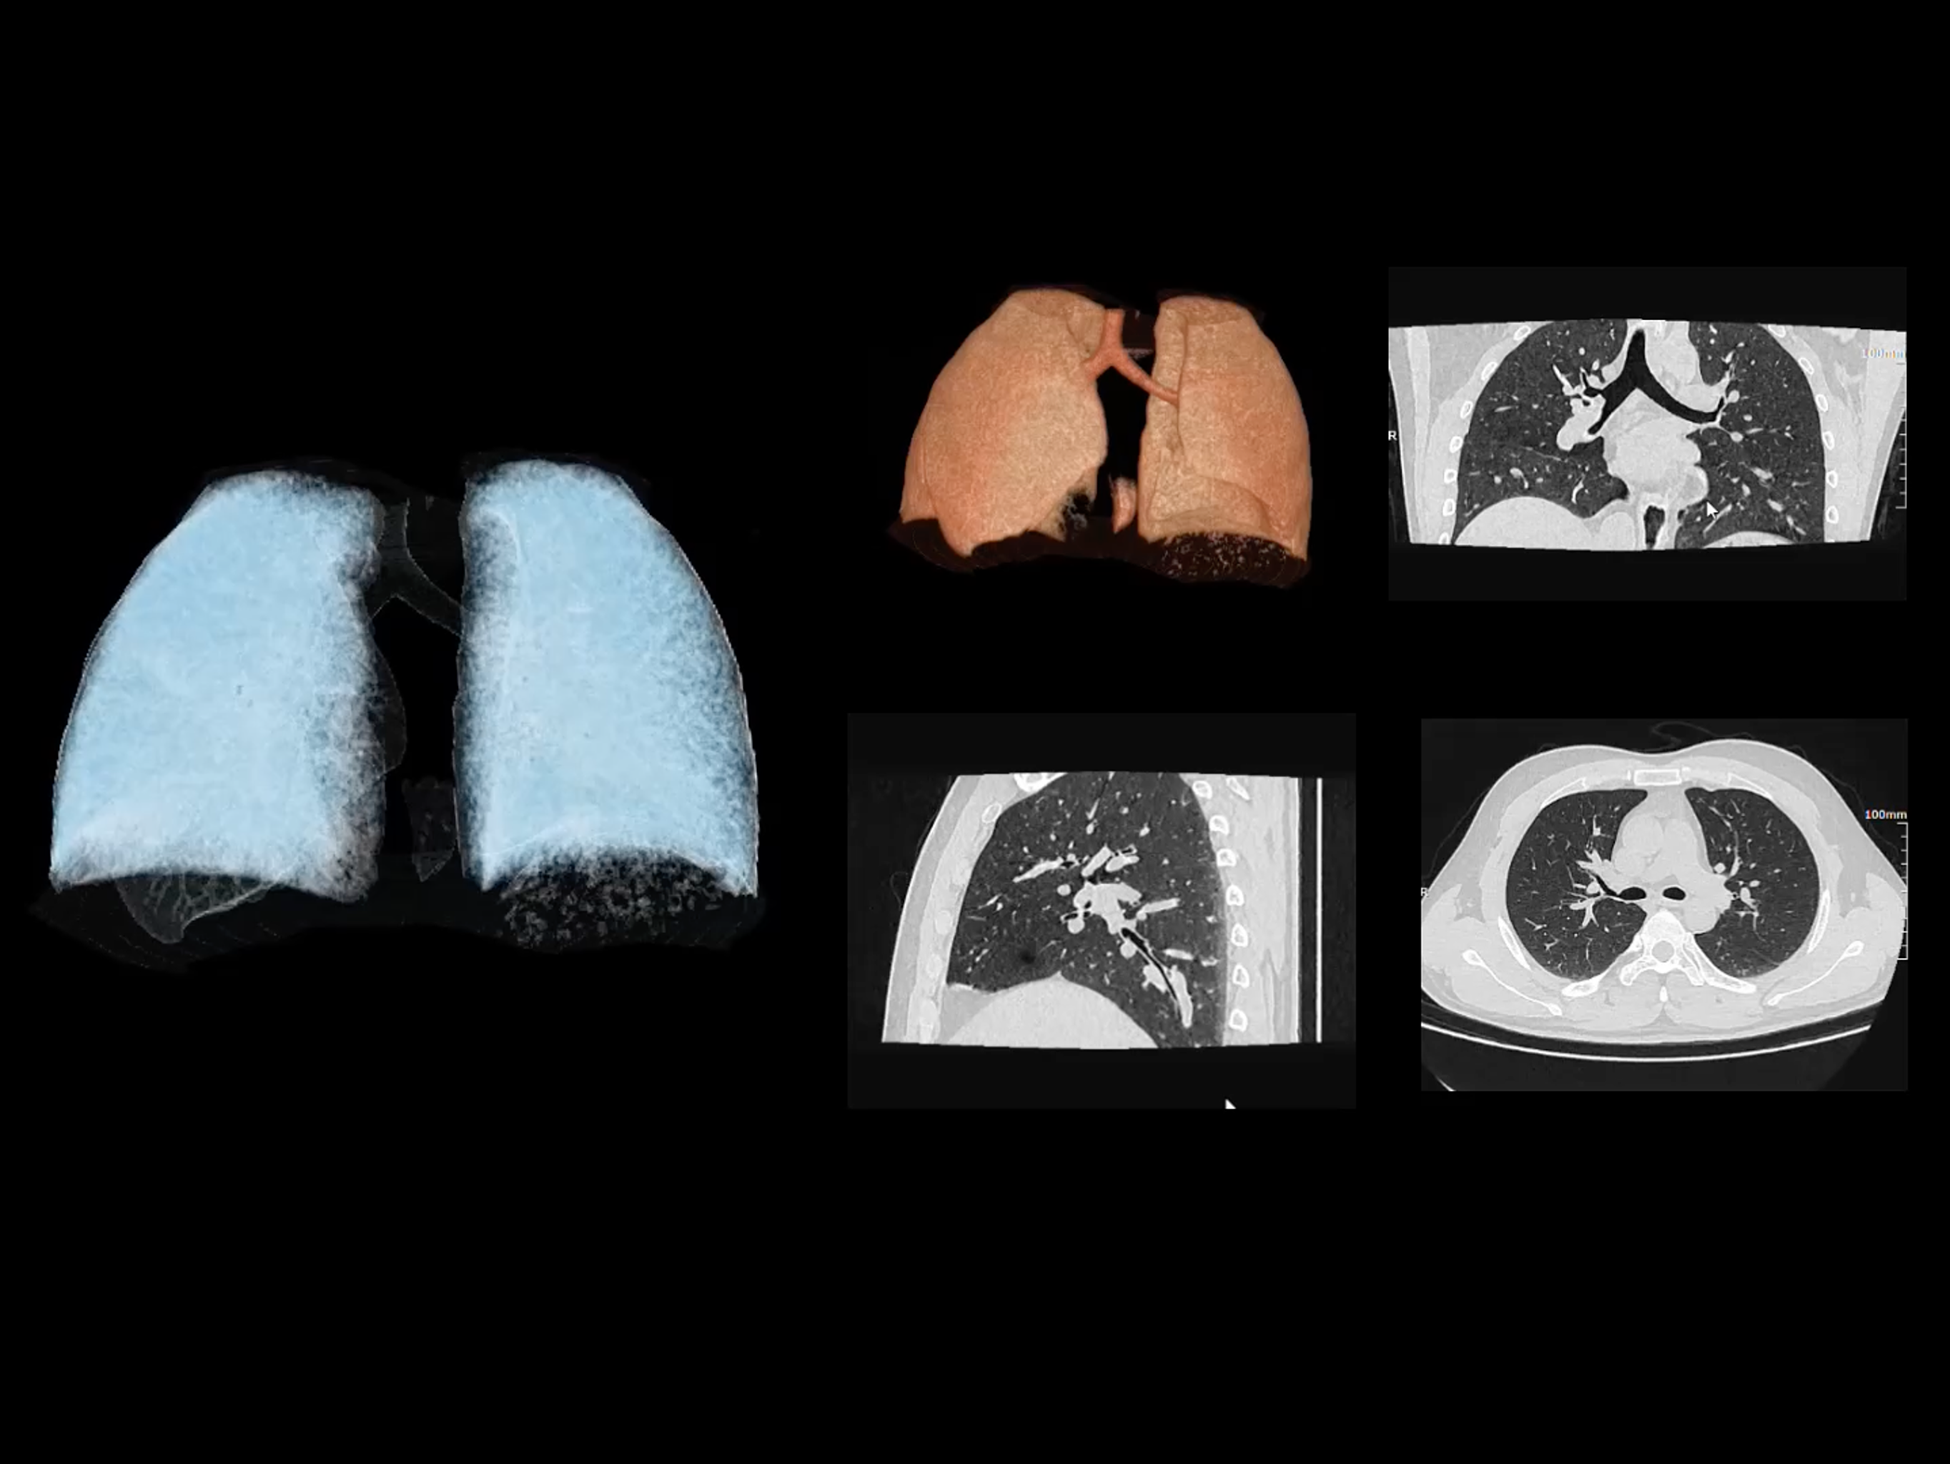

uCT SiriuX® 依托16cm超宽探测器与双源能谱技术,实现真正意义上的全身高清能谱成像。单次扫描同步获取灌注、能谱等多维定量参数,精准解析组织特性与病灶成分,为临床决策提供更深层次的诊断依据。

能谱成像可揭示丰富的物质与能量信息,其临床价值的充分释放有赖于完善高效的后处理分析平台。uCT SiriuX® 提供全面能谱高级分析工具,覆盖心血管、肿瘤、神经、骨科等多类临床场景。平台支持动脉增强分数分析(AEF)、细胞外容积分析(ECV)、肿瘤同源性分析、肺栓塞分析、骨髓水肿分析等多项评估,并提供多达10种基物质对成像,为精准诊断与科研探索提供坚实支撑。